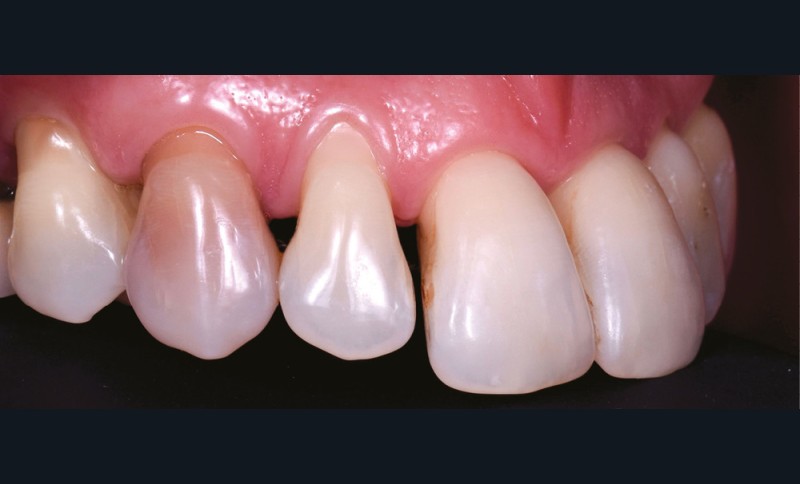

– la nécrose, qui va donner une coloration plutôt brune [3] (fig. 1, 2) ;

– le trauma, qui va donner une couleur plutôt rouge [4] (fig. 3) ;